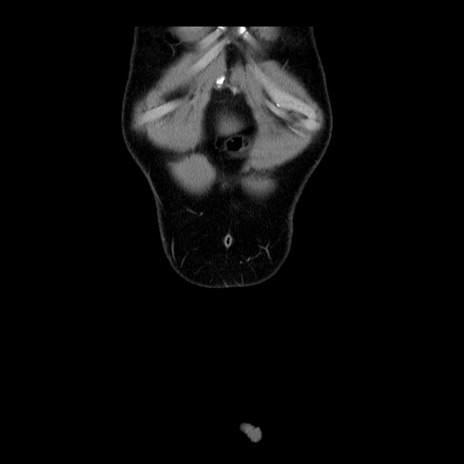

症例4(冠状断像)

【症例】30歳代男性

【主訴】腹痛、嘔吐

【現病歴】昨晩から突然の腹痛あり、その後嘔吐、軟便も出現。腹痛が改善しないため救急搬送となる。2日前にしめ鯖の食事歴あり。

【身体所見】意識清明、苦悶様、BP 135/90mmHg、BT 35.7℃、腹部:平坦、やや硬、心窩部〜臍部に自発痛、圧痛あり、筋性防御+、反跳痛-

【データ】WBC 8100、CRP 0.57